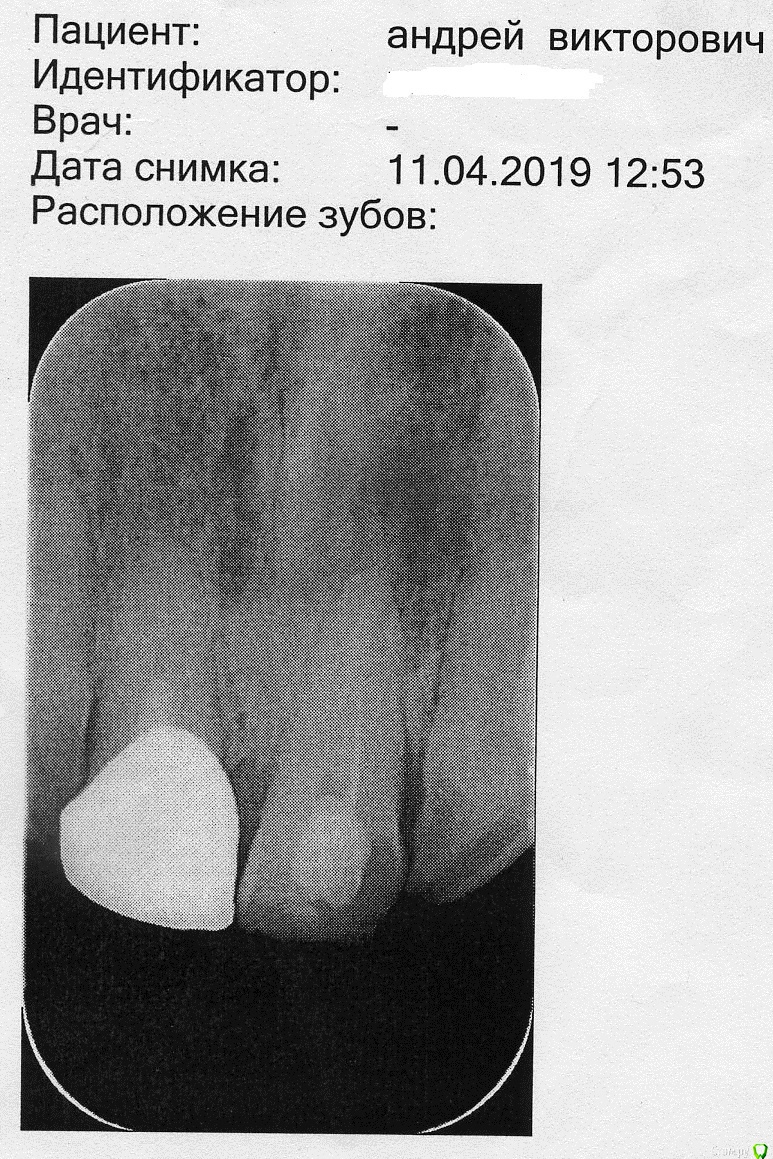

Андрей67 Опубликовано 12 марта, 2020 Поделиться Опубликовано 12 марта, 2020 С год назад обнаружил на десне шишку. Не болела и не беспокоила. В апреле 2019 пошел к врачу у которого лечусь давно и ему, в принципе, доверяю. Зуб рассверлили, почистили, положили лекарство. Так продолжалось раз 5. Потом поставили постоянную пломбу.(снимки №1 и №2)Для перестраховки сходил к лицевому хирургу, показал снимки, посмотрел, пощупал и сказал, что всё нормально. Говорит, что такая опухоль проходит долго, до полугода. Вроде как со временем и меньше стала, потом опять больше. Вернее, день ото дня размер может меняться, то больше то меньше.В феврале этого года оять пошел к своему врачу. Сделали снимок (снимок №3) Говорит, странно, что не рассосалось. Но раз не болит и не мешает, так и живи. Да, пригласила хирурга для консультации. Он сказал, что может разрезать и почистить, но гарантии никакой не даёт.Диагноз ставят - киста. Так ли это на самом деле? Нужно ли лечение и какое или так жить? Ссылка на комментарий